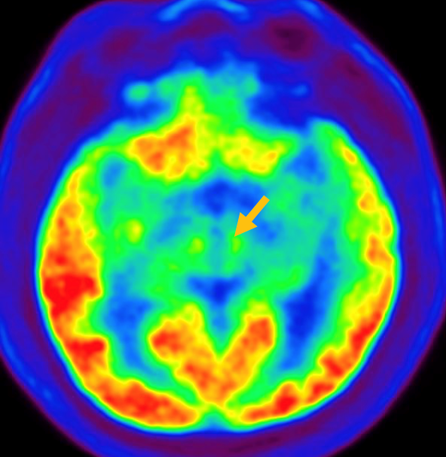

다계통 위축이란 뇌의 다양한 계통에서 위축이 발생하는 것을 의미합니다. 파킨슨 증상이 있으면서 질병 초기에 소변 장애나 기립성 저혈압으로 인한 어지러움이 두드러지게 나타나는 경우, 보행 시 비틀거림이나 구음 장애와 같은 소뇌 위축에 따른 운동 실조 증상이 나타나는 경우, 꿈에서 하는 행동을 수면 중에 보이는 렘수면 행동 장애가 동반되는 경우 다계통 위축을 의심합니다. 다계통 위축은 파킨슨병과 달리 안정 시 떨림이 잘 보이지 않고, 증상이 대칭적인 경우가 많으며, 진행이 빠르며, 레보도파와 같은 항파킨슨 약제에 잘 반응하지 않습니다. 다계통 위축은 뇌 자기공명영상(MRI)에서 교뇌에 십자 모양의 고음영이 나타날 수 있는데, 이를 십자무늬 빵(hot cross bun) 징후라고 합니다. 또한 초기에서는 뇌 자기공명영상(MRI)이 정상으로 보이더라도 뇌포도당 양전자 단층촬영(PET)에서는 소뇌 또는 기저핵의 대사 기능이 저하된 상태가 관찰될 수 있습니다. 이러한 영상 소견은 특징적인 임상 증상과 함께 진단에 참고할 수 있습니다.

[다계통위축 환자의 뇌포도당 양전자 단층 촬영에서 확인되는 소뇌의 대사 기능 저하]